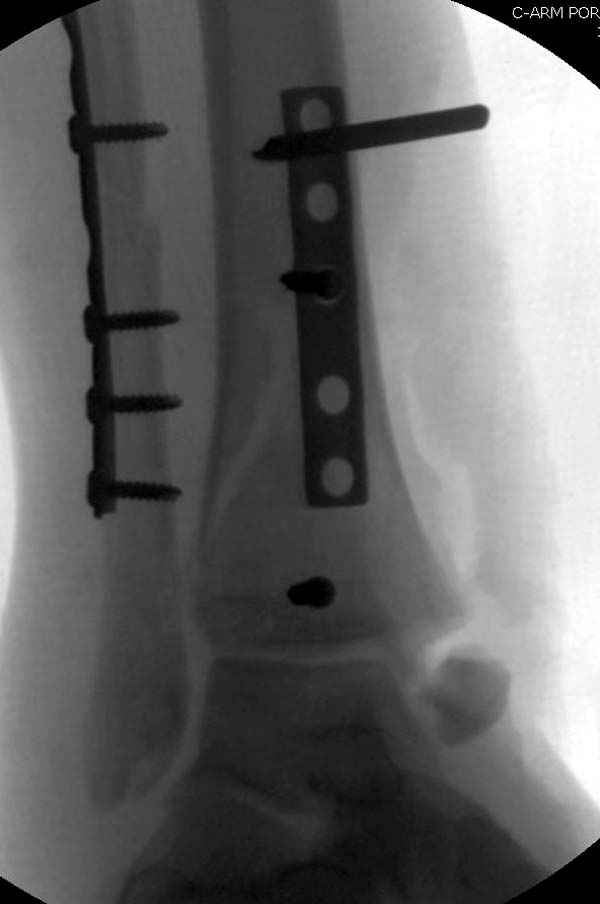

Уважаемые коллеги! Помогите определится с тактикой лечения.Оскольчатый импрессионный перелом заднего края правой большеберцовой (Пилон?) кости 5-ти недельной давности на фоне неправильно сросшихся переломов пяточных костей (травма в 1991г.), ДОА подтаранных суставов 3 ст. До последней травмы больная ходила без особых проблем и работала пекарем (работа на ногах).Суть проблемы в том, что открытая анатомическая репозиция в таком сроке представляется мне крайне травматичной, что может привести к неблагоприятному функциональному исходу.Варианты решения:1) оставить "как есть" с последующим артродезом после развития ДОА2) выполнить остеотомию и попытаться низвести основную часть суставной поверхности3) выполнить попытку анатомической репозиции из задне-латерального??? доступа.

По снимкам довольно сохранный сустав, и такой сустав желательно попытаться восстановить всеми возможными мерами.

Насчет пилона, прошло достаточное время для консолидации и прекрасная возможность для демонстрации, что такие случаи могут быть успешно вылечены остеотомией, несмотря на засторелость.

Из заднего доступа остеотомия тонким остеотомом и коррекции на ЭОПе.

Без применения сложной конструкции, а обычными параллельными шурупами. Шурупы в 3.5 мм и дополнительно фиксация крючковидной пластиной, сделанной из 3.5 mm semitubular пластиной, Butress или аntiglade фиксация.

Здесь алгоритм фиксации свежего перелома и преоперационный план для обсуждаемого случая.